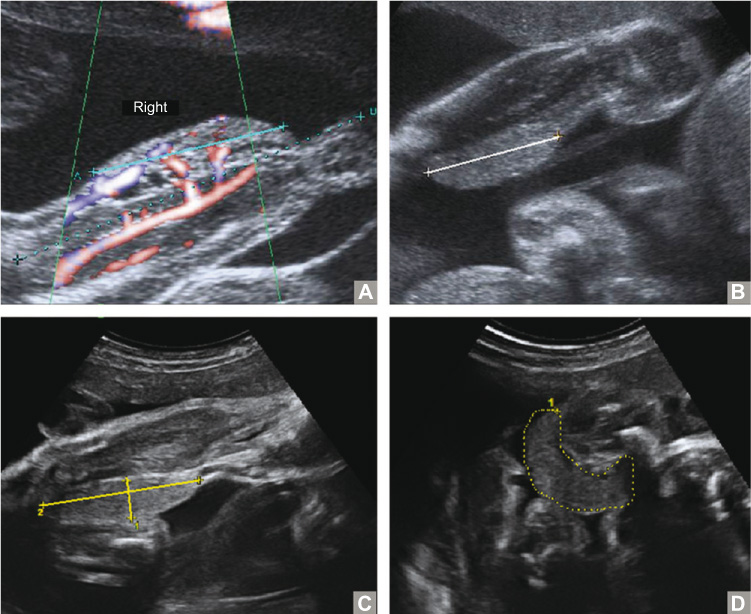

At 23+1 weeks of gestation, ultrasound (US) examination showed a homogeneous soft tissue mass (~2.7×0.8 cm) of the right lower leg in one of the fetuses, with multiple feeding arteries and drained by the popliteal vein, suggestive of a hemangioma (Figure 1A and B). US examination at 29+6 weeks of gestation showed moderate insufficiency of the tricuspid valve, and Doppler examination revealed increased flow in the umbilical vein with a normal pulsatility index of the ductus venosus. Biometry of both fetuses was appropriate for gestational age. During follow-up, the mass increased to a size of 1.5×5.0×4.0 cm at 32+6 weeks of gestation (Figure 1C and D). Despite previous signs of hyperdynamic circulation, the child did not develop cardiac decompensation and circulation parameters turned normal. At that time, on basis of these findings, the lesion was suspected to be a congenital hemangioma (CH). The parents were informed about the possible diagnoses and the benign course of these lesions. Close antenatal follow-up was advised using US to score the size and the development of the lesion. The professionals involved were informed about the risks during and after delivery and a cesarean section (CS) was advised.

US images.

(A) First US at 23+1 weeks of gestational age showing a mass on the mediodorsal side of the right lower leg, ~2.7 cm in length (cyan line). Doppler imaging shows extended vascularity of the lesion with afferent and efferent vessels. (B) On US at 28+6 weeks of gestation, the well-defined homogeneous soft tissue mass has extended to a length of 3.9 cm (white line). (C) US at 32+6 weeks of gestation showing an increasing size of ~1.5×5 cm (yellow lines). (D) On the same US, incomplete circumferential growth of the tumor is visible (circumference 11.3 cm, yellow dotted line).